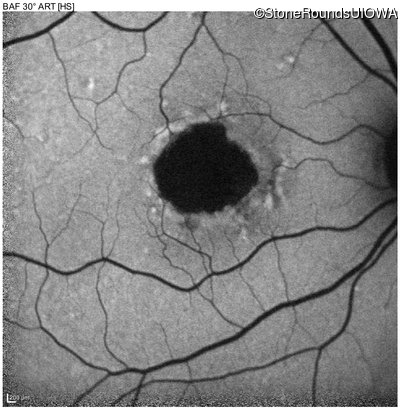

Infrared Fundus Photograph - Right - 20/40 +1 sc

Exemplar